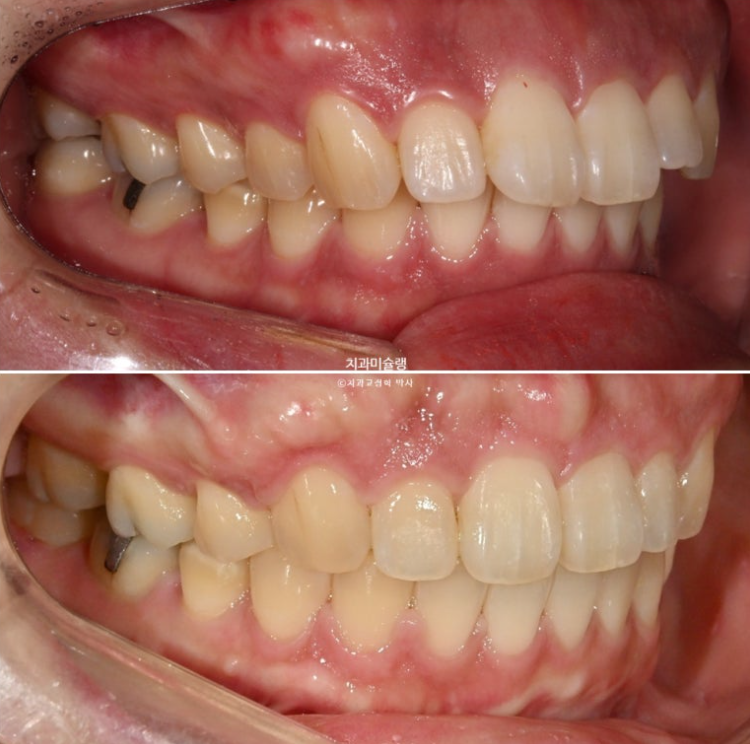

The midline and deep overbite have improved.

A stable, secure occlusal relationship is a given.

Let’s compare the before and after.

If you compare the before-and-after photos, you can see that the previously flat gum area above the front teeth has become uneven.

It is easy to misunderstand this as bone growing and protruding more than before, but in fact, the protruding part is the original position of the bone from before treatment, when the gums were protruding.

When the front teeth are successfully moved backward, including the roots, the gum bone covering the tooth roots also naturally resorbs and moves backward together with the roots. This is the process by which gum protrusion is resolved.

However, some areas of gum bone stubbornly remain in their original position and do not resorb.

As a result, these areas can look relatively protruded compared with the surrounding area after treatment, and this is the reason why the gums sometimes look uneven after extraction orthodontics.

After treatment, the angulation of the front teeth is good.